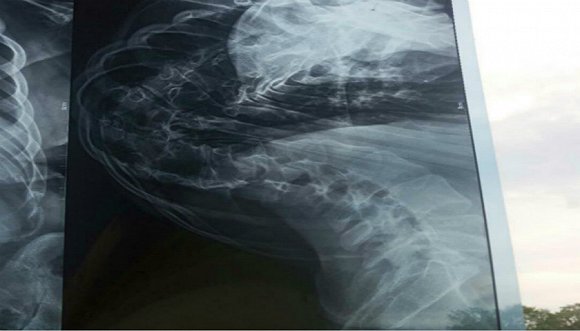

從側面拍攝的傅月的脊柱CT圖像。圖片來源:受訪者提供